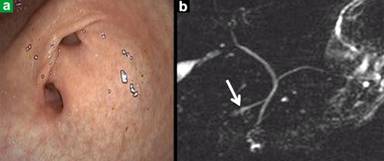

A twenty two-year-old woman was admitted to our hospital because of mild epigastric pain. Her medical history was unremarkable. The laboratory tests that were requested on admission were normal except for amylase 920 U/L (reference range: 60-180 U/L).The patient denied having had any history of PUD or of having used nonsteroidal anti-inflammatory drugs (NSAIDs). A UE examination revealed two pyloric openings into the duodenal bulb. However, there was no evidence of PUD on the UE. The presence of Helicobacter pylori was not observed in the histological examination of the gastric antrum tissue. Magnetic resonance cholangiopancreatogram (MRCP) imaging showed PD (Figure 1ab). The patient was treated symptomatically, and she recovered. When the UE and MRCP were repeated for control on the sixth month of the treatment, they demonstrated the same findings as the initial UE and MRCP.

Figure 1. a. Endoscopic appearance of double pylorus. b. MRCP appearance of pancreas divisum. Typically, the accessory duct drains majority of pancreas (white arrow). |

In our case, the MRCP showed ventral duct draining of the pancreas. Because of the normal mucosal findings of the gastric antrum and the duodenal bulb on the UE, as well as the negative history of PUD or of any use of NSAIDS, we diagnosed this patient as having DP associated with PD.